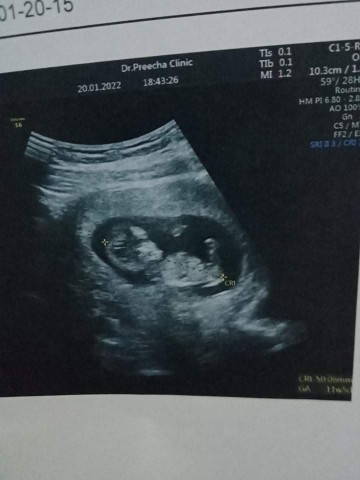

11+5. น้องเเข็งเเรงดีมากคะ หมอบอกน้องตัวใหญ่มาก